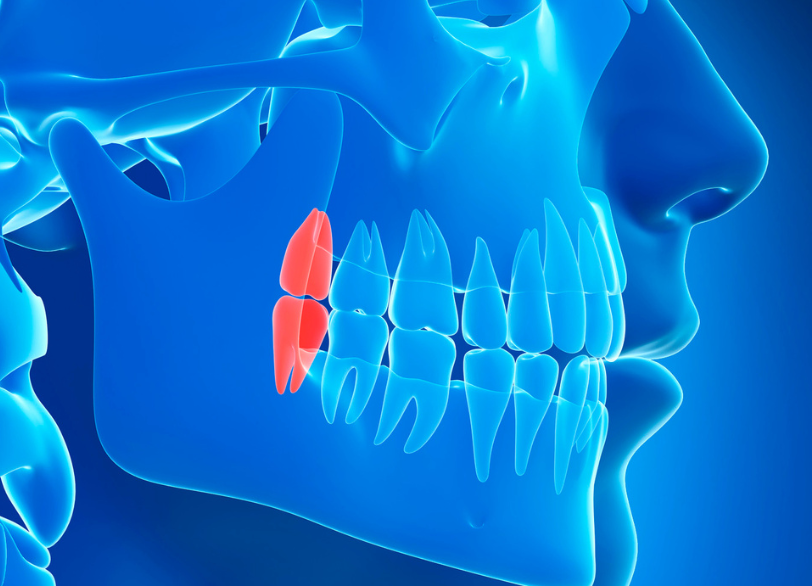

親知らずの抜歯

抜くべきか、残すべきか、正しい判断を

親知らず(第三大臼歯)は前歯から数えて8番目、最も奥に生えてくる永久歯です。

しかし、現代人は顎が小さくなっている傾向があり、親知らずが正常に生えるスペースが不足しているケースが大半です。

斜めに生えたり、骨の中に埋まったままだったりすることで、周囲の歯や歯ぐきに悪影響を及ぼしている場合は、抜歯を強く推奨します。

抜歯を推奨するケース

歯並びを悪化させている

親知らずが横向きに生え、手前の歯をグイグイと押している場合、歯列全体が乱れる原因になります。

特に矯正治療を行う前や、矯正後の後戻りを防ぐために抜歯が必要になることがあります。

親知らずの抜歯、特に骨の中に埋まっている「埋伏智歯(まいふくちし)」の抜歯は、高度な技術を要する外科手術です。